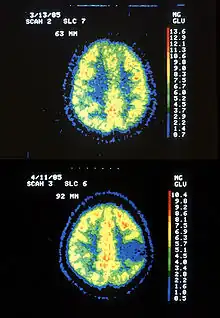

- Friedreich's ataxia: Manifestation: Local cerebral metabolic activity is increased extensively as the disease progresses.[3]

- ↑ Gilman; et al. "Cerebral Glucose Hypermetabolism in Friedreich's Ataxia Detected with Positron Emission Tomography" (PDF). Annals of Neurology. American Neurological Association. Retrieved 29 November 2012.